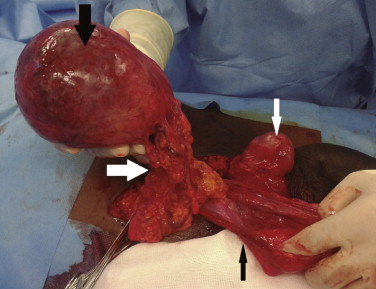

Microscopically, the tumor was a mesenchymal, spindled hypocellular proliferation, with cytonuclear atypia sparse or absent. These cells were in a stromal matrix containing small to medium sized blood vessels, composed of thick, eosinophilic collagen fibers with an admixture of thinner and lighter collagen fibers. Necrosis or mitotic figures were absent (Fig. 2 ). Immunohistochemical analysis showed that the neoplastic cells reacted positively with vimentin (Fig. 3 ) and focally with desmin. Immunoreactivity was negative for: smooth muscle actin, CD117, B-catenin, ALK, CKAE1-AE3, CA5.2, Calretin, WT1, trombomodulin, S100, CD68, CD99, bcl2 and IgG4.

Photomicrograph of the tumor reveals a mesenchymal, spindled hypocellular ...

Figure 2.

Photomicrograph of the tumor reveals a mesenchymal, spindled hypocellular proliferation in a stromal matrix, containing small to medium size blood vessels, composed by thick, eosinophilic collagen fibers (white arrow) with an admixture of more thin and light collagen fibers (black arrow) (hematoxylin-eosin, ×100).